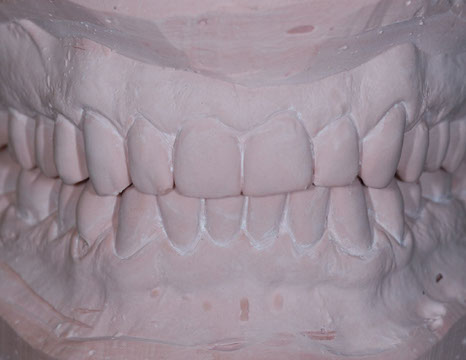

due impronte della bocca da cui si ricaveranno dei modelli in gesso

Nei ragazzi di età superiore (quando la maggior parte dei denti permanenti sono in arcata) e negli adulti, si interviene con trattamenti fissi mirati sia alla risoluzione delle malposizioni dentarie, sia alla correzione degli incongrui rapporti intermascellari in modo da allineare i denti e migliorare l'estetica raggiungendo una buona funzione masticatoria.